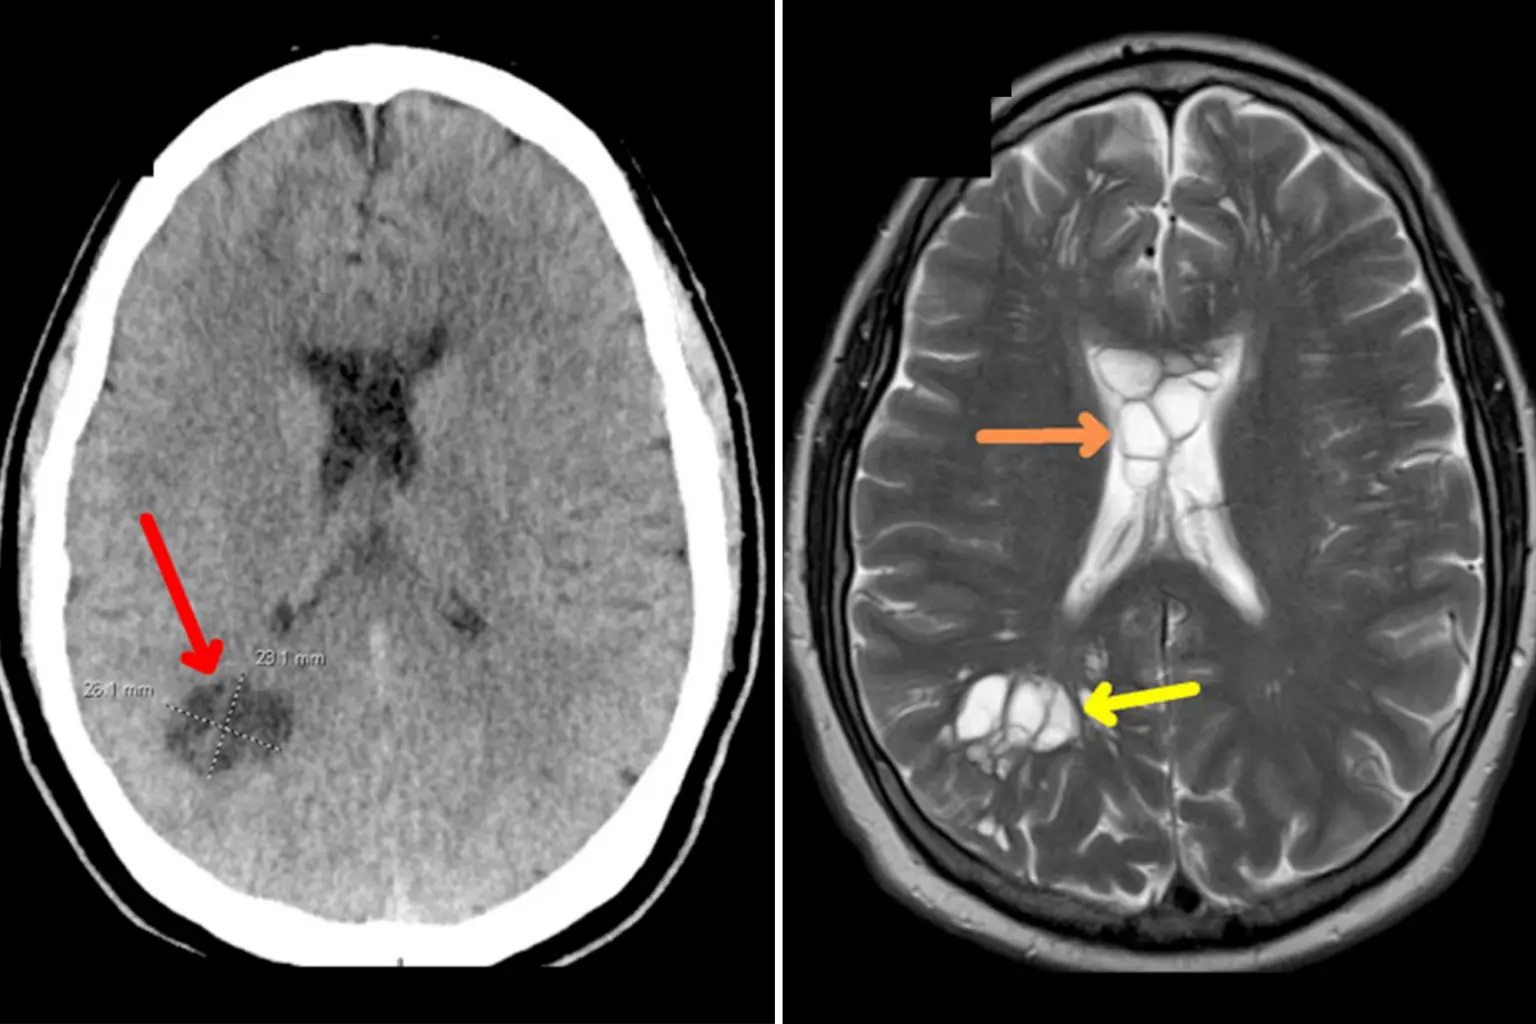

Στην συγκεκριμένη περίπτωση, ο ασθενής εκτός από το οίδημα, ανέπτυξε κύστεις και στις δύο πλευρές του εγκεφάλου του. Αργότερα, αυτό αποδείχθηκε ότι προκλήθηκε από τo παράσιτο (κεστοειδής σκώληκας) που είχε γεννήσει αυγά μέσα στον εγκέφαλο του άνδρα.